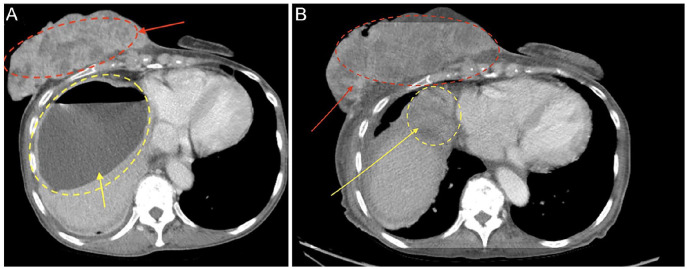

The introduction of screening mammograms has revolutionized the early detection of breast cancer. However, it remains the most common cancer in women in the United States, excluding skin cancer. As the incidence rates continue to rise, unusual presentations have become more frequent. Additionally, healthcare barriers can lead to delayed detection of breast cancer, resulting in unexpected complications. The occurrence of pyogenic liver abscess (PLA) in diabetic cancer patients, due to the synergistic effect of insulin-like growth factor-1 in tumorigenesis and abscess formation, is well documented. PLA is also prevalent in hepatocellular, colorectal, and pancreato-biliary tumors. However, the occurrence of PLA as an initial presentation of isolated advanced breast cancer without these comorbidities is understudied. This may be due to direct spread of infection from affected skin or spread via lymphatics or vasculature in the setting of immunosuppression from cancer. We present an exceedingly rare case of PLA, complicated by pulmonary embolism, in an elderly female with newly diagnosed stage IIIB breast carcinoma.